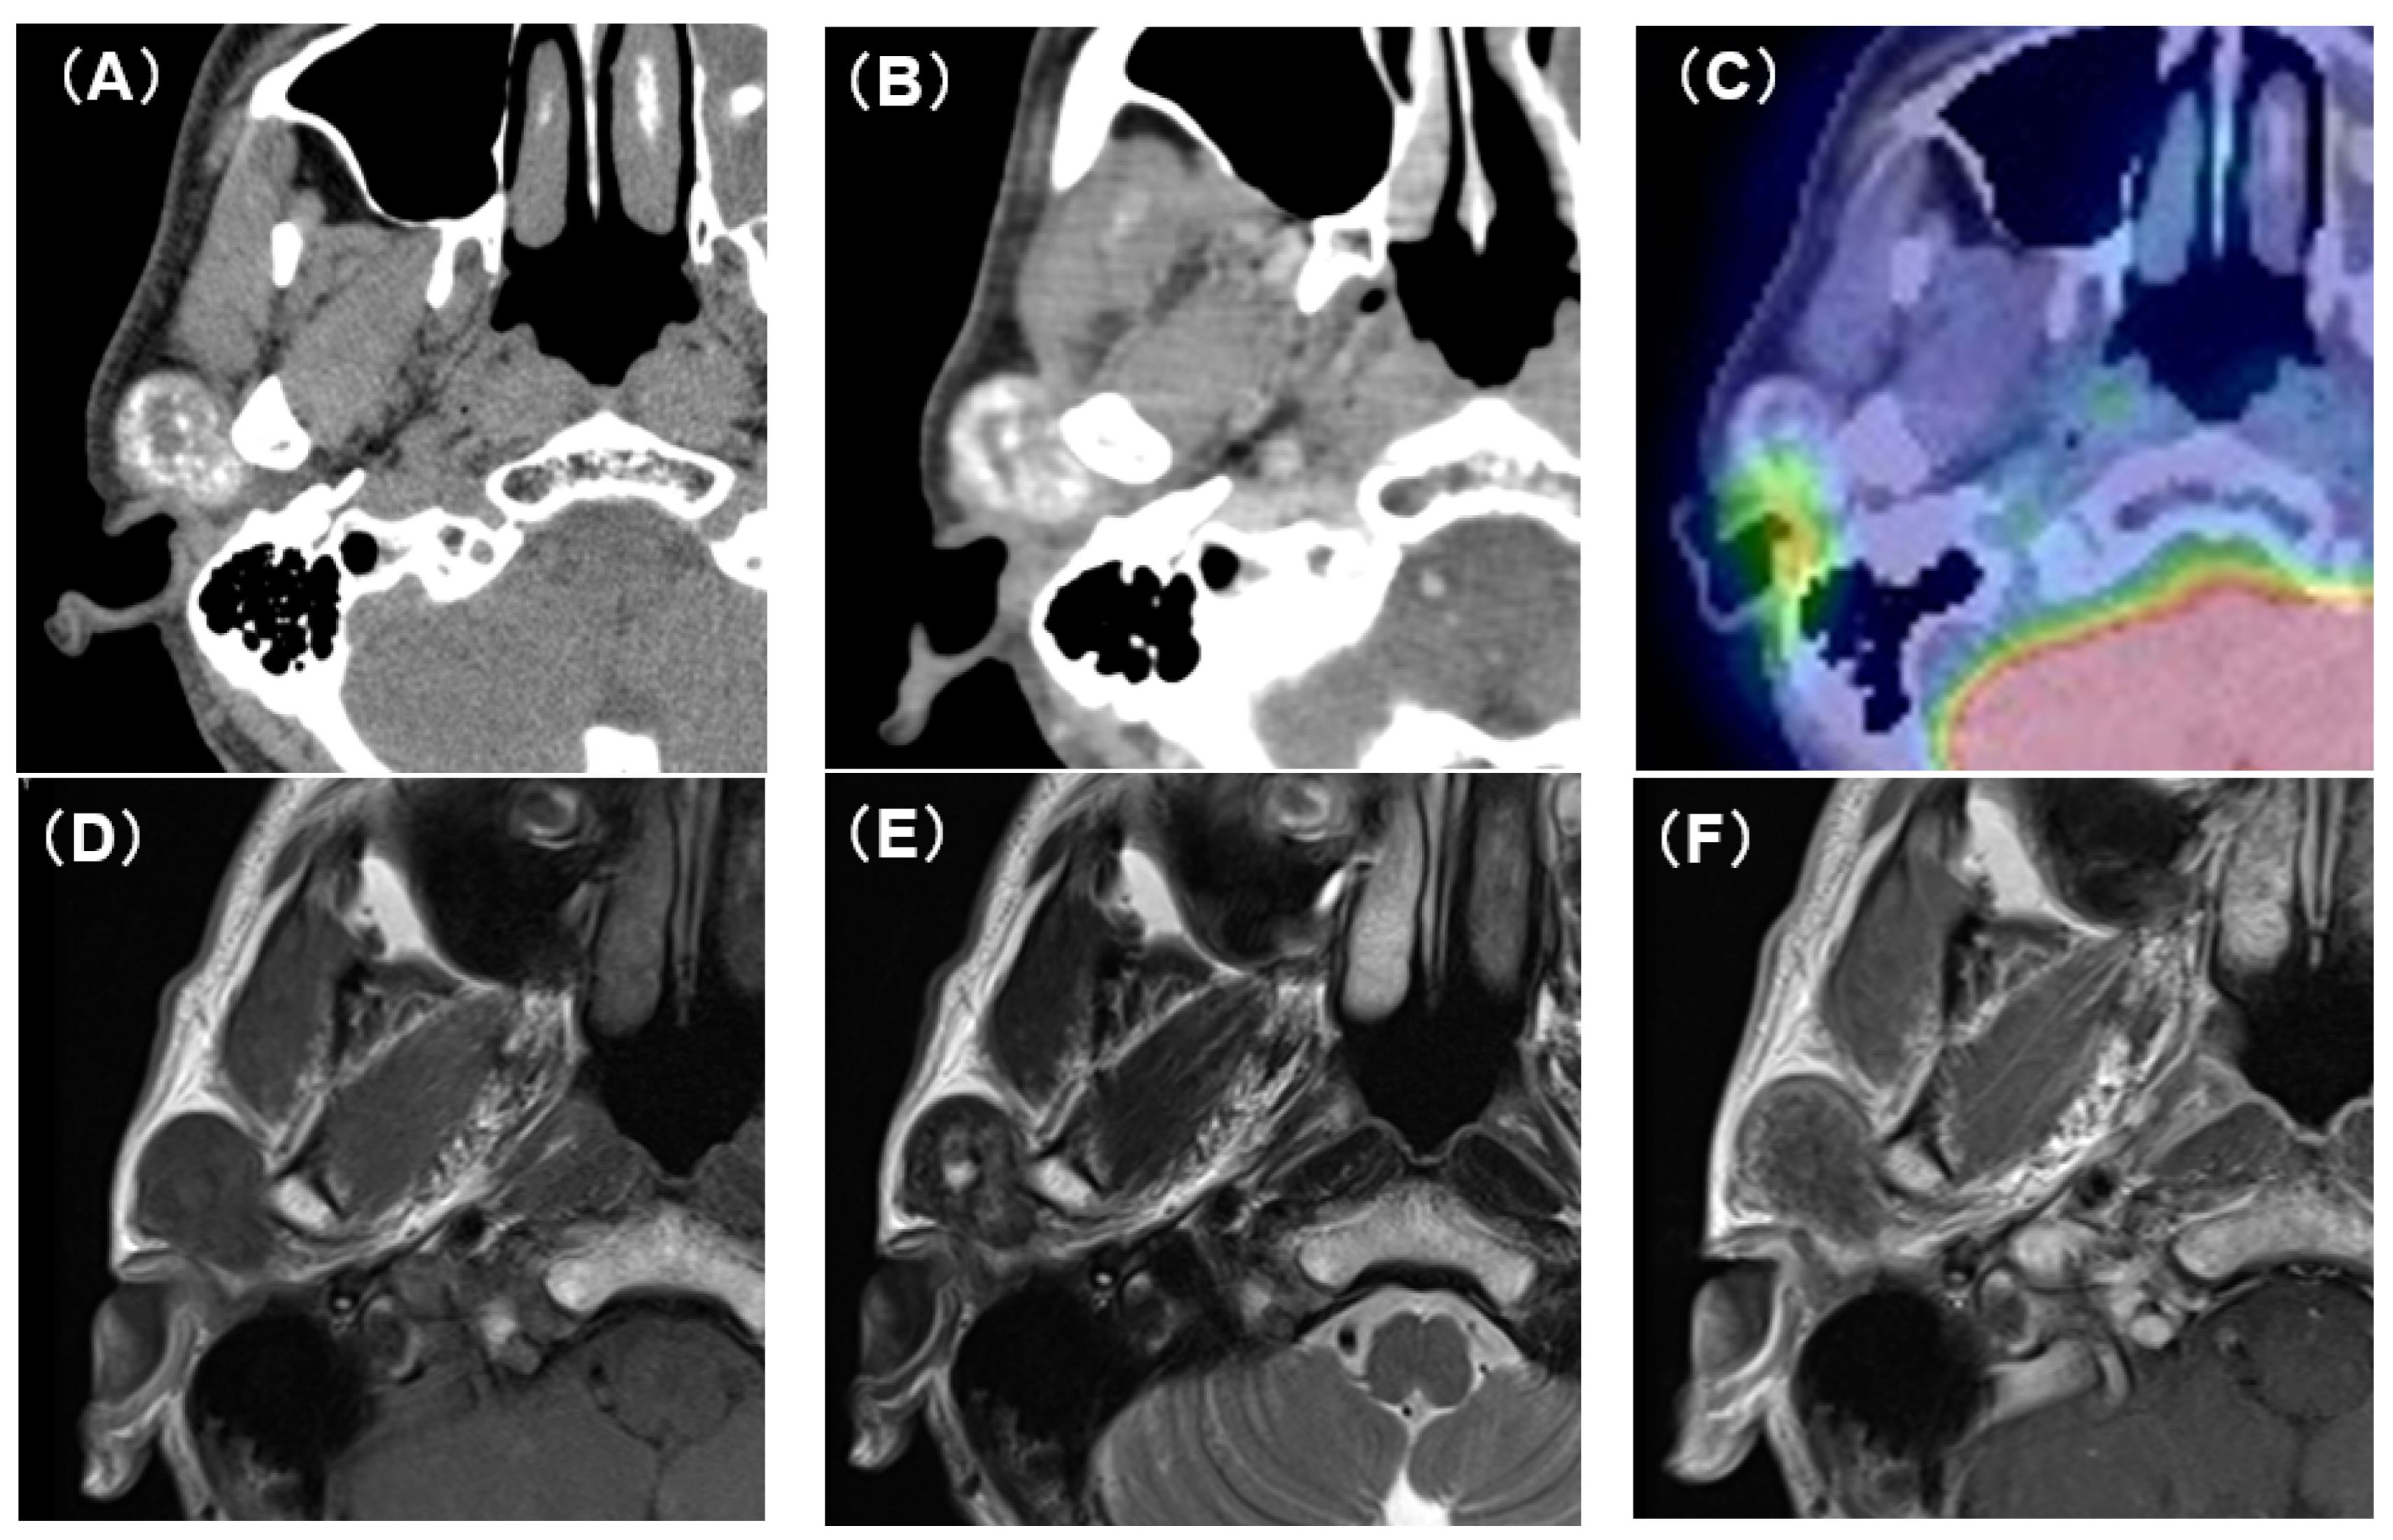

Computed tomography (CT) showed an oval tumor in the region of the right TMJ, extending to the upper pole of the parotid gland. The tumor was oval-shaped with an actual width of 2.5 cm and a length of 3 cm. It had well-defined borders and a diffuse hyper-absorptive zone within, which indicated diffuse calcification (Figure 1A,B). Positron emission tomography with 18F-fluorodeoxyglucose (18F-FDG-PET) showed a mild uptake of 18F-FDG (SUVmax = 3.25) (Figure 1C). There was no uptake in other sites except for physiological uptake. The tumor showed a poor contrast effect with iodine-based contrast medium. A magnetic resonance image (MRI) showed a well-defined mass in the upper pole of the right parotid gland. T1-weighted images showed a low-signal tumor (Figure 1D), while T2-weighted images showed a low-signal tumor with a macular high-signal area (Figure 1E). The contrast effect of gadolinium was poor (Figure 1F). Fine-needle aspiration cytology confirmed only neutrophils and histiocytes; there were no definitive findings.

Figure 1.

CT, PET-CT, and MRI findings. (A) Plain CT horizontal section. The inside of the tumor is diffusely accompanied by a high-density area. (B) Contrast-enhanced CT horizontal section. The contrast enhancement effect of the tumor is poor. (C) PET-CT image findings. The tumor showed mild uptake of 18F-FDG (SUVmax = 3.25). (D) Plain MRI T1 image findings. The tumor is visualized as an area of uniform low-intensity. (E) Plain MRI T2 image findings. Low-intensity mass lesion with faint patchy hyperintensity inside. (F) Contrast-enhanced MRI T1 image findings. The tumor enhancement with gadolinium was poor.